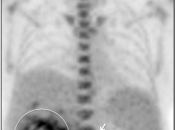

- Maximum Intensity Projection (MIP)

- 3-D Rotating MIP & Coronal “Quick MIP”